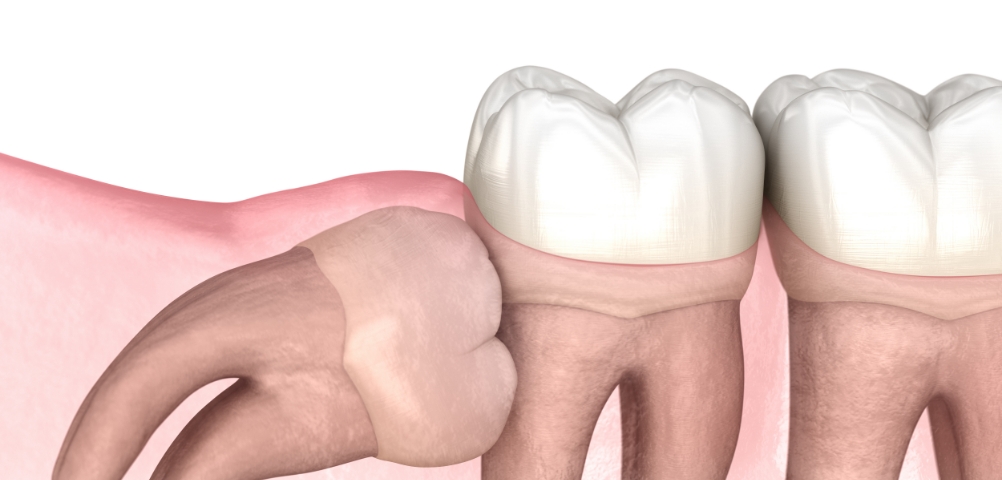

3D CT로 사랑니의 방향, 신경 위치, 주변 치아와의 관계를 세밀하게 확인한 뒤 필요한 경우에 한해 발치를 진행합니다.

불필요한 조직 손상을 최소화하는 방식으로 부담을 줄이며, 환자분이 보다 편안하게 회복하실 수 있도록 돕고 있습니다.